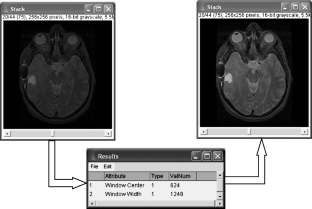

The demand for image-processing software for radiology applications has been increasing, fueled by advancements in both image-acquisition and image-analysis techniques. The utility of existing image-processing software is often limited by cost, lack of flexibility, and/or specific hardware requirements. In particular, many existing packages cannot directly utilize images formatted using the specifications in part 10 of the DICOM standard (“DICOM images”). We show how image analyses can be performed directly on DICOM images by using ImageJ, a free, Java-based image-processing package (http://rsb.info.nih.gov/ij/). We demonstrate how plug-ins written in our laboratory can be used along with the ImageJ macro script language to create flexible, low-cost, multiplatform image-processing applications that can be directed by information contained in the DICOM image header.